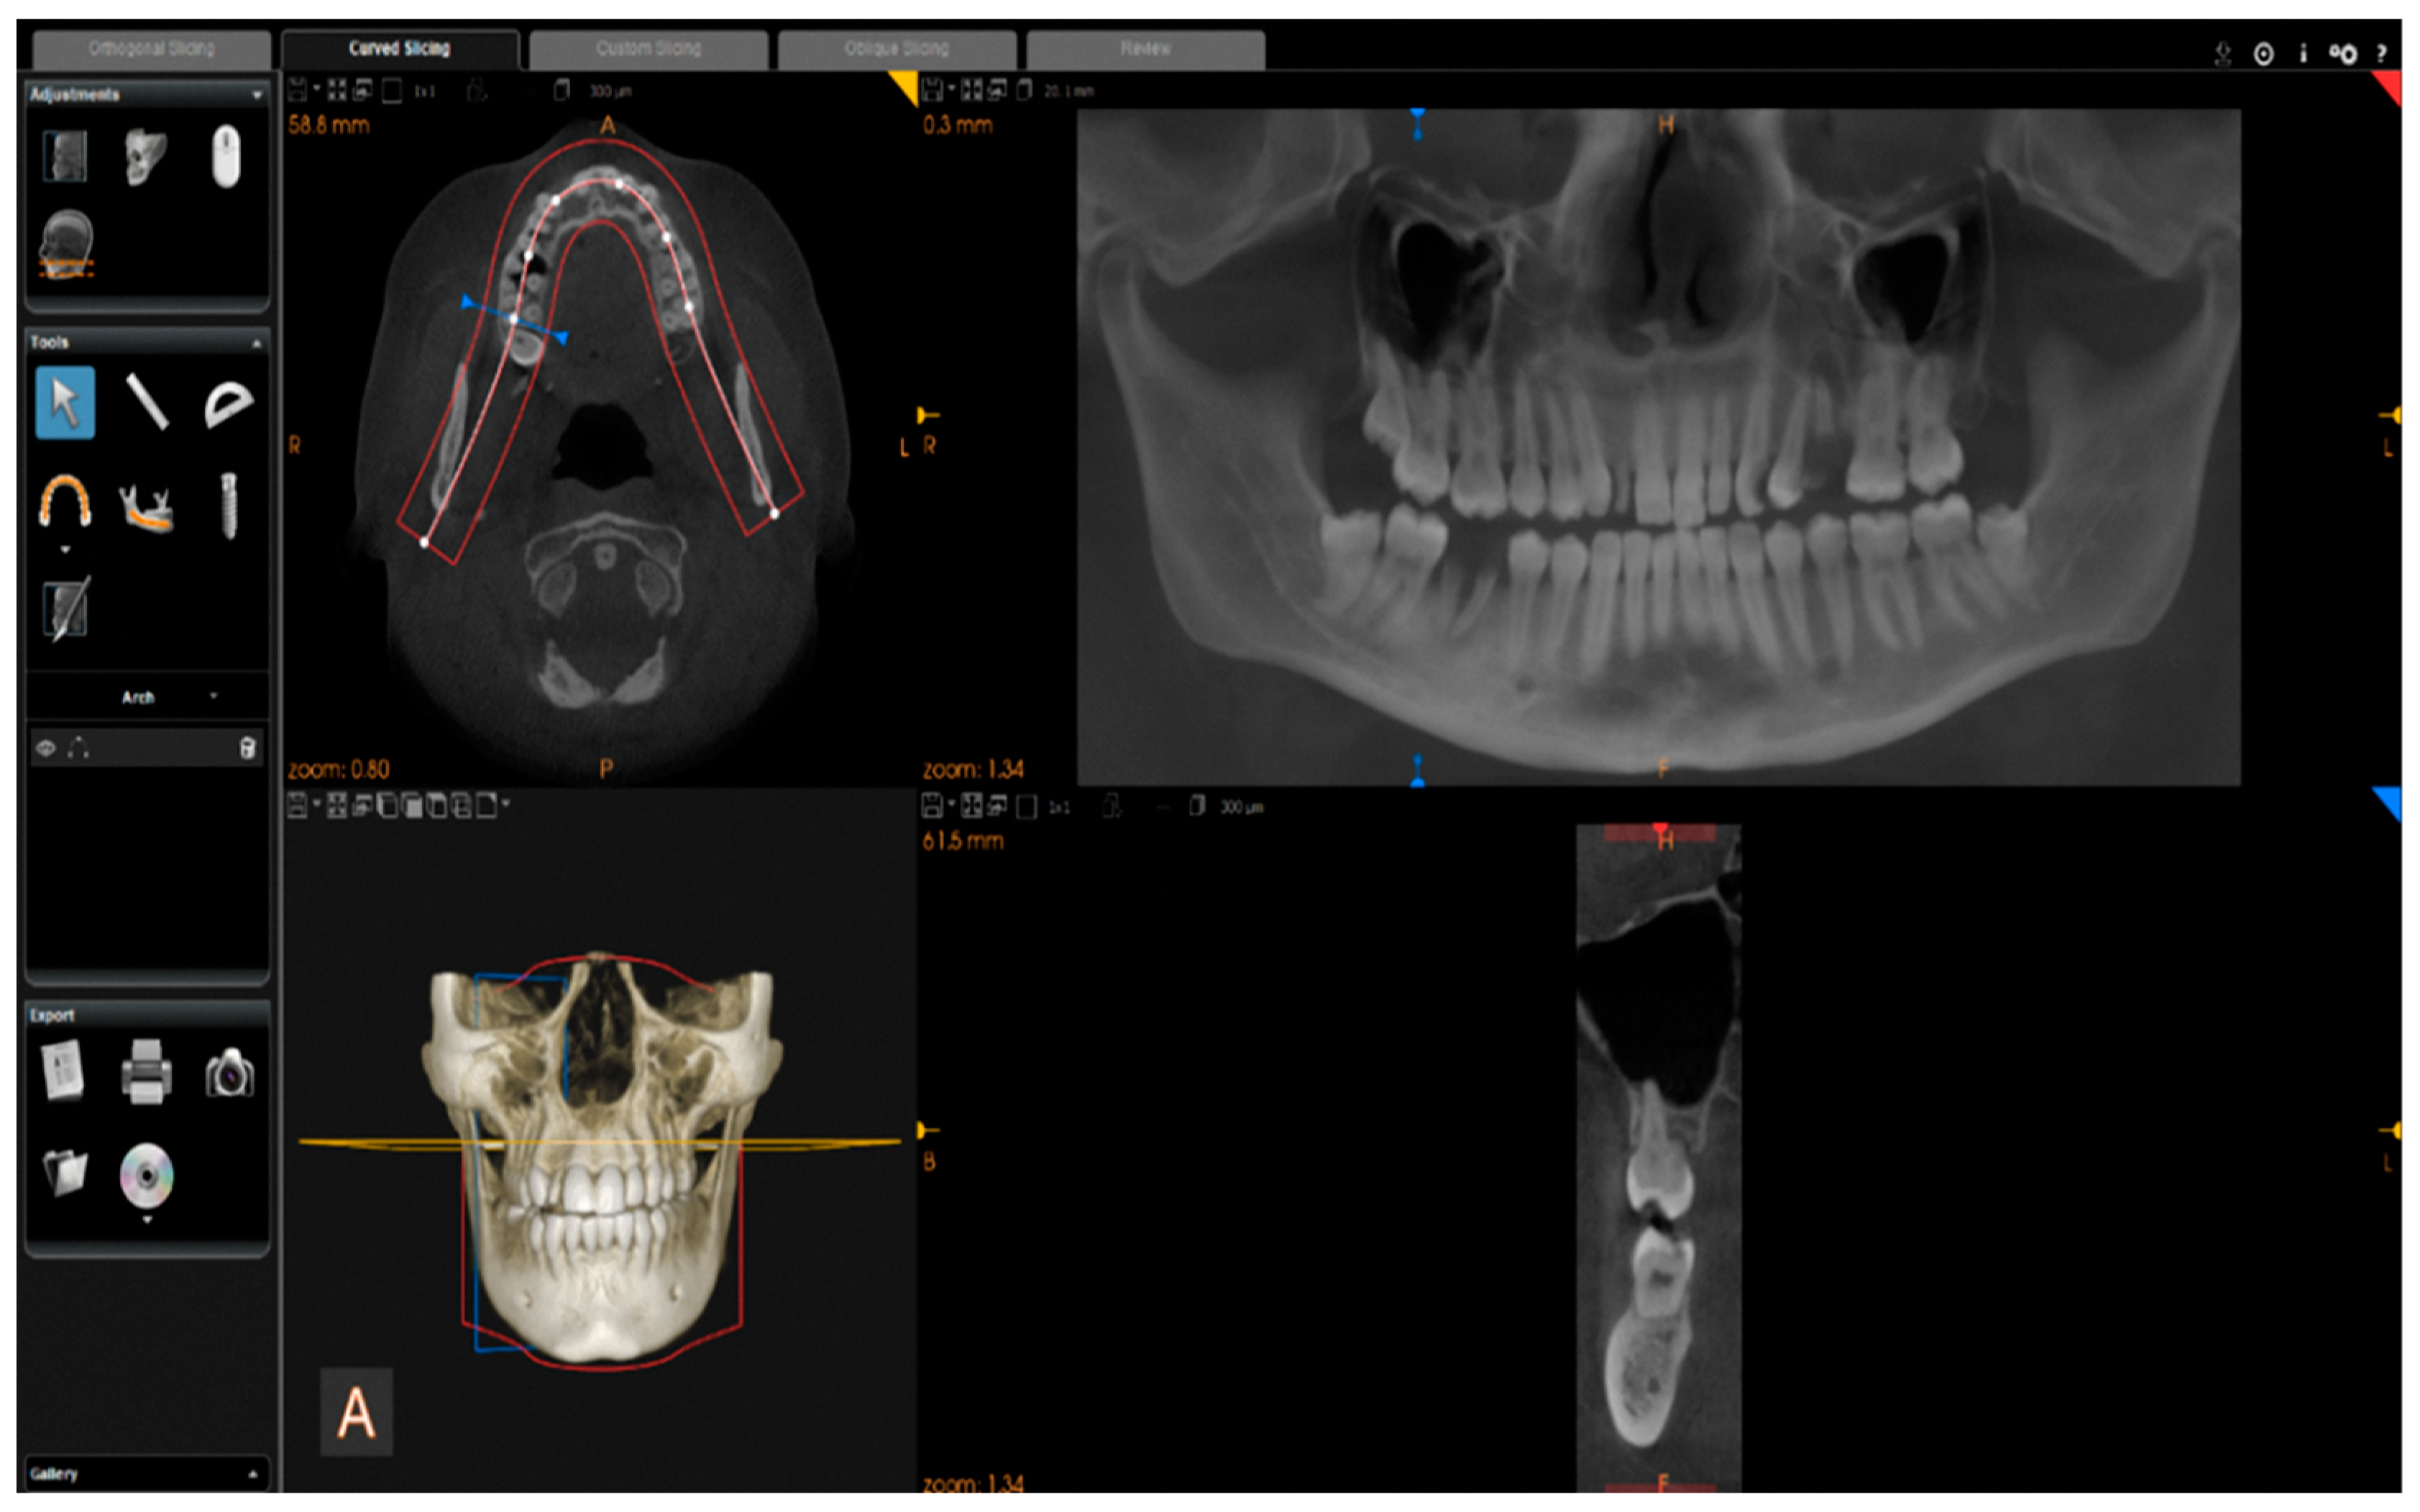

Images were reconstructed in C.S. 3D Imaging Software (Carestream Dent L.L.C., Atlanta, GA, USA). The head positions were standardized anteroposteriorly and sagittally according to a standard method. From CBCT volumes, the panoramic images were reconstructed by selecting a custom focal trough that passed through the lingual cusps of the maxillary teeth and extended posteriorly to the condyles. (Figure 2).

Figure 2.

Reconstruction of panoramic images from CBCT volumes.